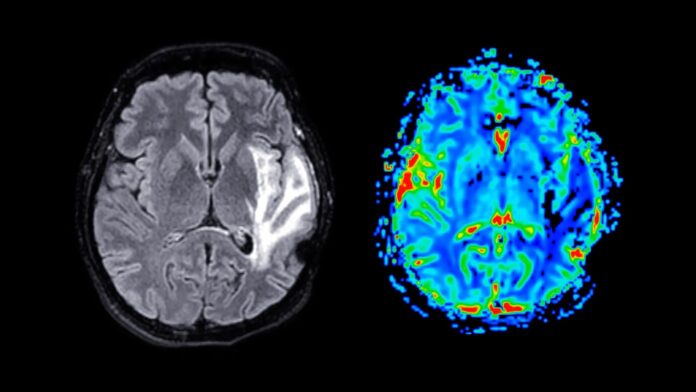

Cambiamenti nella struttura del cervello

Le scansioni MRI hanno mostrato che le donne in post-menopausa avevano un volume ridotto di materia grigia nell’ippocampo (formazione della memoria), nella corteccia entorinale (elaborazione delle informazioni) e nella corteccia cingolata anteriore (regolazione emotiva). Queste regioni sono vulnerabili anche nel morbo di Alzheimer, portando i ricercatori a ipotizzare che la menopausa potrebbe aumentare il rischio di demenza a lungo termine nelle donne. La professoressa Barbara Sahakian, autrice senior, sottolinea che, sebbene non conclusiva, questa scoperta aiuta a spiegare perché alle donne viene diagnosticata la demenza con un tasso quasi doppio rispetto agli uomini.